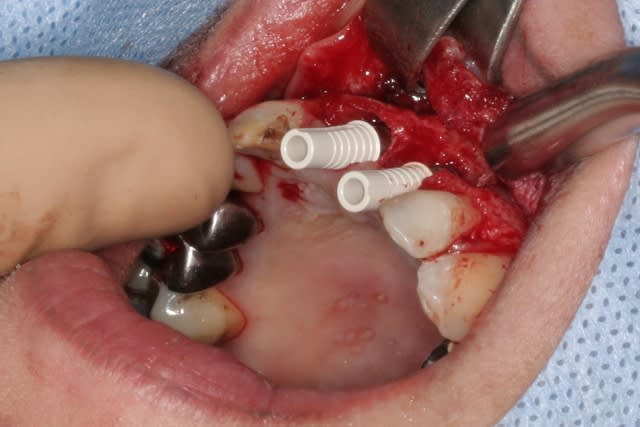

tien, ce matin, extraction de 24/25, curetage méticuleux, forage, comblement du gap, pose des 2 implants qui se sont bloqués à 50Ncm au CA sur les 3 ou 4 mm apicaux, pose des vis de cicat, sutures...35min....tranquille...

Purée, tu prends des risques énormes en fourrant ton bio oss puis en vissant les implants dans la masse de bio oss, de un, et sans membraner l'interface pilier implant, de deux...

Je suis peut-être vieux jeu mais c'est, à mon avis, dangereux d'un point de vue bactériologique.

c'est pas la première fois que je fais çà...;-)

et çà me donne plutôt de bons résultats

après tout...le périoste n'est-il pas la meilleure membrane?

par contre il faut veiller à avoir une bonne étanchéité au niveau des sutures...